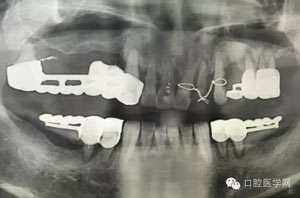

病例1:患者迫切希望保留自己的這一顆牙齒,根尖周陰影比較大,二度松動(dòng).而且旁邊有種植修復(fù)體,和患者溝通好后,治療好后觀察一個(gè)月后冠修復(fù),因?yàn)橛蟹N植的后期修復(fù),所以有了機(jī)會(huì)觀察,術(shù)后三個(gè)月和術(shù)后四個(gè)月,根尖恢復(fù)的還算不錯(cuò),希望能夠繼續(xù)觀察下去.這樣子的病例,做的時(shí)候我們一定要非常的小心,和患者要有充分的溝通以及不同科室的溝通然后決定怎么樣做比較好,假如就是出現(xiàn)了問(wèn)題,到時(shí)候我們也比較好處理些,免得我們自己到時(shí)候不好收?qǐng)觥?/span>